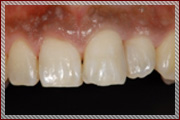

審美歯科

歯を白くしたい!

患者様の状態によりさまざまな治療方法があります。

当院では患者様とご相談しながら数種類の方法を提案させていただき、

ご納得いただける方法でご安心いただける治療を提供いたします。

治療の際も顕微鏡など拡大鏡下で行うことにより、自然できれいな仕上がりになります。

セラミック治療

自然の歯は、白く輝いて見えます。しかし人工の歯でも自然の美しさに近い状態で、歯としての機能を回復させ、健康的で美しい歯を取り戻すことが出来ます。

自然な感じで、見た目(審美的)にも機能的にも満足のいく、人工セラミックの歯は金属アレルギー対策にもなります。

審美歯科は、特に審美性に配慮した治療法です。

従来の虫歯や歯周病といった、歯や歯肉の病気を治すことが目的ではなく、もう一歩進んで、美しく健康な歯や歯肉を作ることを目的としています。

そして何よりも、自分の笑顔に自身を持ち、より快適で楽しい生活を送っていただくための治療です。

当院の審美歯科の特徴

01.精度の高い補綴治療が可能

当院では、歯科技工士が常駐しているため、精度の高い補綴治療が可能です。

必要に応じて院内で患者様のお口を直接確認し、色合わせや使用感などの確認ができることが強みです。

02.スピーディーな対応

当院では、セレックシステムを導入しています。セレック治療を行うことで、治療で来られた当日に補綴物をご提供できる「ワンデイトリートメント」も可能です。忙しく、歯科医院にあまり通えない方へも無理なく通って頂けます。